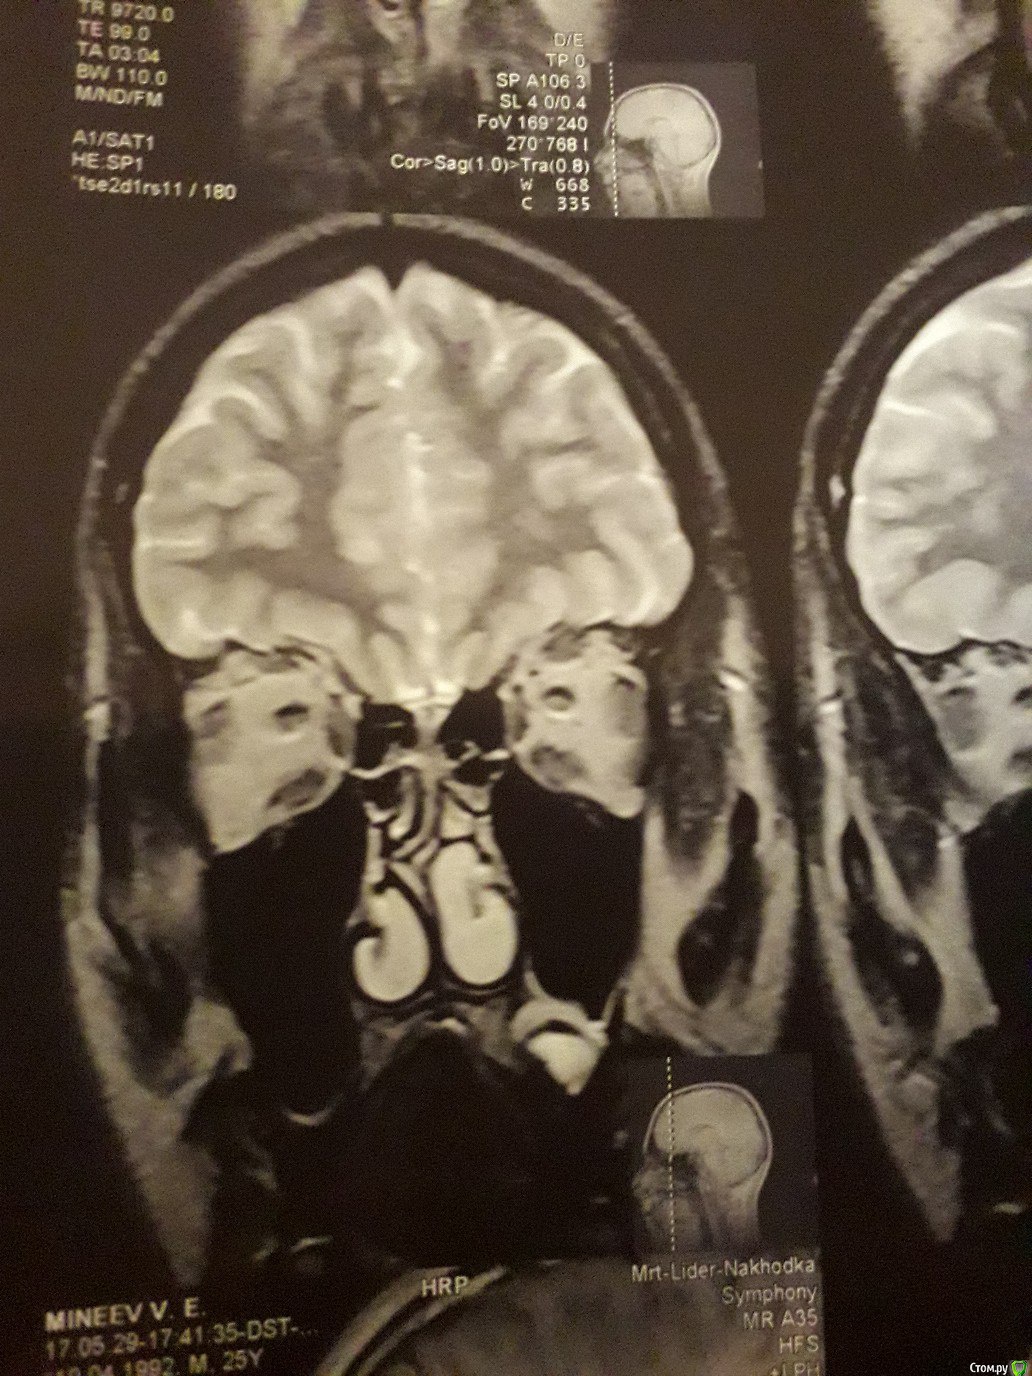

Виталий000000001 Опубликовано 30 сентября, 2017 Поделиться Опубликовано 30 сентября, 2017 Здравствуйте. На корне 26-го зуба киста вросшая в гайморову.Одни врач посоветовал удалить;Второй - не трогать и понаблюдать, если не беспокоит;А третий хирург сказал, что при удалении зуба, такая большая киста останется в кости и продолжит расти и что такое лечится только операцией на гайморовой.Подскажите что делать с кистой. Ссылка на комментарий

red_butler Опубликовано 1 октября, 2017 Поделиться Опубликовано 1 октября, 2017 По этим снимкам ничего не скажешь. Делайте кт на стоматологическом томографе 1 Ссылка на комментарий

IvanK Опубликовано 2 октября, 2017 Поделиться Опубликовано 2 октября, 2017 Перфорируется ли гайморова при удалении этого зуба?скорее нет, чем да По этим снимкам ничего не скажешь. Делайте кт на стоматологическом томографе+1 Ссылка на комментарий